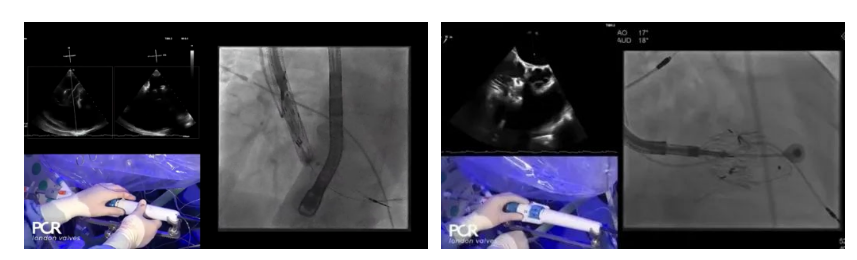

在Thomas Modine教授的線上指導(dǎo)下,德國Mainz中心Ralph Stephan von Bardeleben教授完成了LuX-Valve Plus經(jīng)血管三尖瓣置換系統(tǒng)在其所在中心的首例植入,術(shù)后Stephan教授高度贊揚(yáng)LuX-Valve Plus人工三尖瓣瓣膜“植入過程高度可控,安全有效”。接受治療的是一例82歲的高齡男性患者,術(shù)前NYHAⅢ級,因復(fù)發(fā)心衰入院,有逾5年的慢性房顫病史。這例患者因特殊的解剖結(jié)構(gòu)以及較大的三尖瓣瓣環(huán),有起搏器植入史,被所有其他經(jīng)導(dǎo)管三尖瓣修復(fù)或置換器械的臨床排除在外,因此等了一年半才等到此次LuX-Valve Plus的手術(shù)機(jī)會,實屬不易。

手術(shù)在全麻狀態(tài)下開展,采用經(jīng)右側(cè)頸靜脈入路的方式將輸送器送入患者心臟內(nèi),在TEE及DSA引導(dǎo)下調(diào)整輸送器頭端角度,使得輸送器與三尖瓣瓣環(huán)平面垂直。在輸送器進(jìn)入右心室后釋放室間隔錨定裝置,而后釋放瓣葉夾持件(2個耳片結(jié)構(gòu))成垂直狀態(tài)。在TEE及DSA確定夾持件固定至三尖瓣葉根部且位于右室側(cè)后釋放人工瓣心房側(cè)盤片。隨后調(diào)整瓣膜同軸性以及室間隔錨定件位置(貼合室間隔),前推藏針管并固定,進(jìn)而釋放室間隔錨定裝置,并再次確認(rèn)瓣膜位置、穩(wěn)定性及同軸性,合攏輸送鞘后撤出輸送器,完成LuX-Valve Plus人工三尖瓣瓣膜的植入。